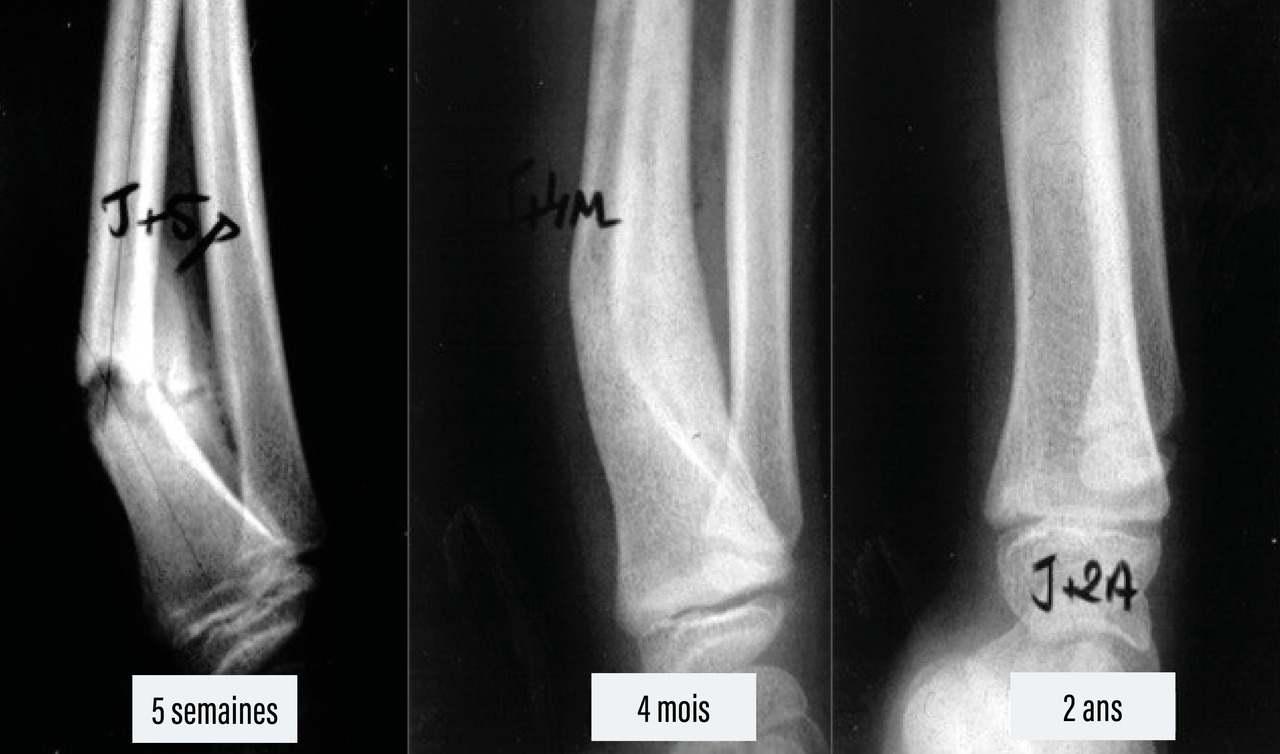

Il permet de remodeler la fracture en effaçant les imperfections de la réduction (fig. 2). Ce remodelage se fait par résorption osseuse dans la convexité et apposition dans la concavité.4

Le cal périphérique produit par le périoste est très volumineux et se constitue rapidement chez l’enfant. Il englobe le foyer de fracture et permet la réalisation plus tardive du cal central, puis du remodelage. Le remodelage du cal se fait par l’apposition d’os par le périoste du côté de la concavité du cal vicieux et par sa résorption du côté de la convexité.

Concernant les fractures à distance du cartilage de croissance, le remodelage du cal et la croissance épiphysaire atténuent, voire corrigent, les éventuels cals vicieux.7

Il y a, par exemple, un fort potentiel de remodelage des fractures du quart inférieur des deux os de l’avant-bras.